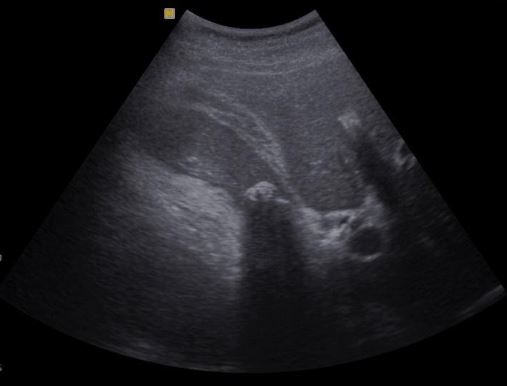

Ultrassom do abdome total demonstrando líquido livre no abdome (ascite) e um fígado retraído e irregular, compatível com cirrose.

Vesícula biliar espessada e com um cálculo em seu interior, compatível com colecistite. Imagem de um exame de ultrassom do abdome total.